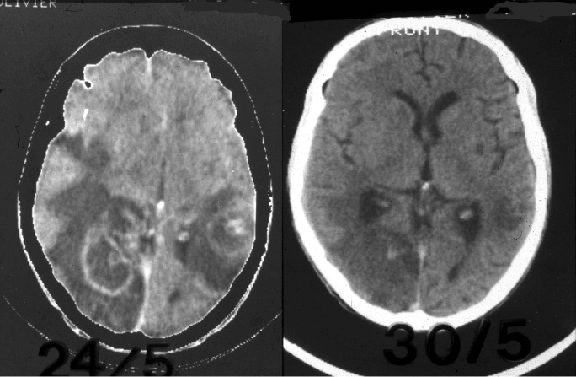

La toxoplasmose cérébrale (infection parasitaire)

Environ 50 % des adultes en France sont séropositifs pour la toxoplasmose. Ce parasite du chaton n’est pas dangereux. Le chat excrète le virus dans ses selles et contamine la litière, l’eau d’arrosage ou encore les ovins et bovins. Le plus souvent retrouvé chez le mouton, ce parasite se loge dans les muscles de l’animal qui seront enkystés.

L’Homme sera donc contaminé en consommant du mouton, notamment pas trop cuit, comme il est consommé en France. Aux États-Unis et en Angleterre, le mouton est respectivement consommé bien cuit et bouilli, la séroprévalence de la toxoplasmose est donc beaucoup plus faible dans ces pays.

La toxoplasmose est dangereuse dans deux circonstances :

- chez la femme enceinte, le parasite peut se localiser chez le bébé et donner des infections sévères ;

- chez les patients atteints du VIH et ayant déjà eu la toxoplasmose plusieurs années auparavant. Dès l’apparition du VIH, le patient devient très immunodéprimé, ce qui réactive la toxoplasmose et provoque des abcès cérébraux.